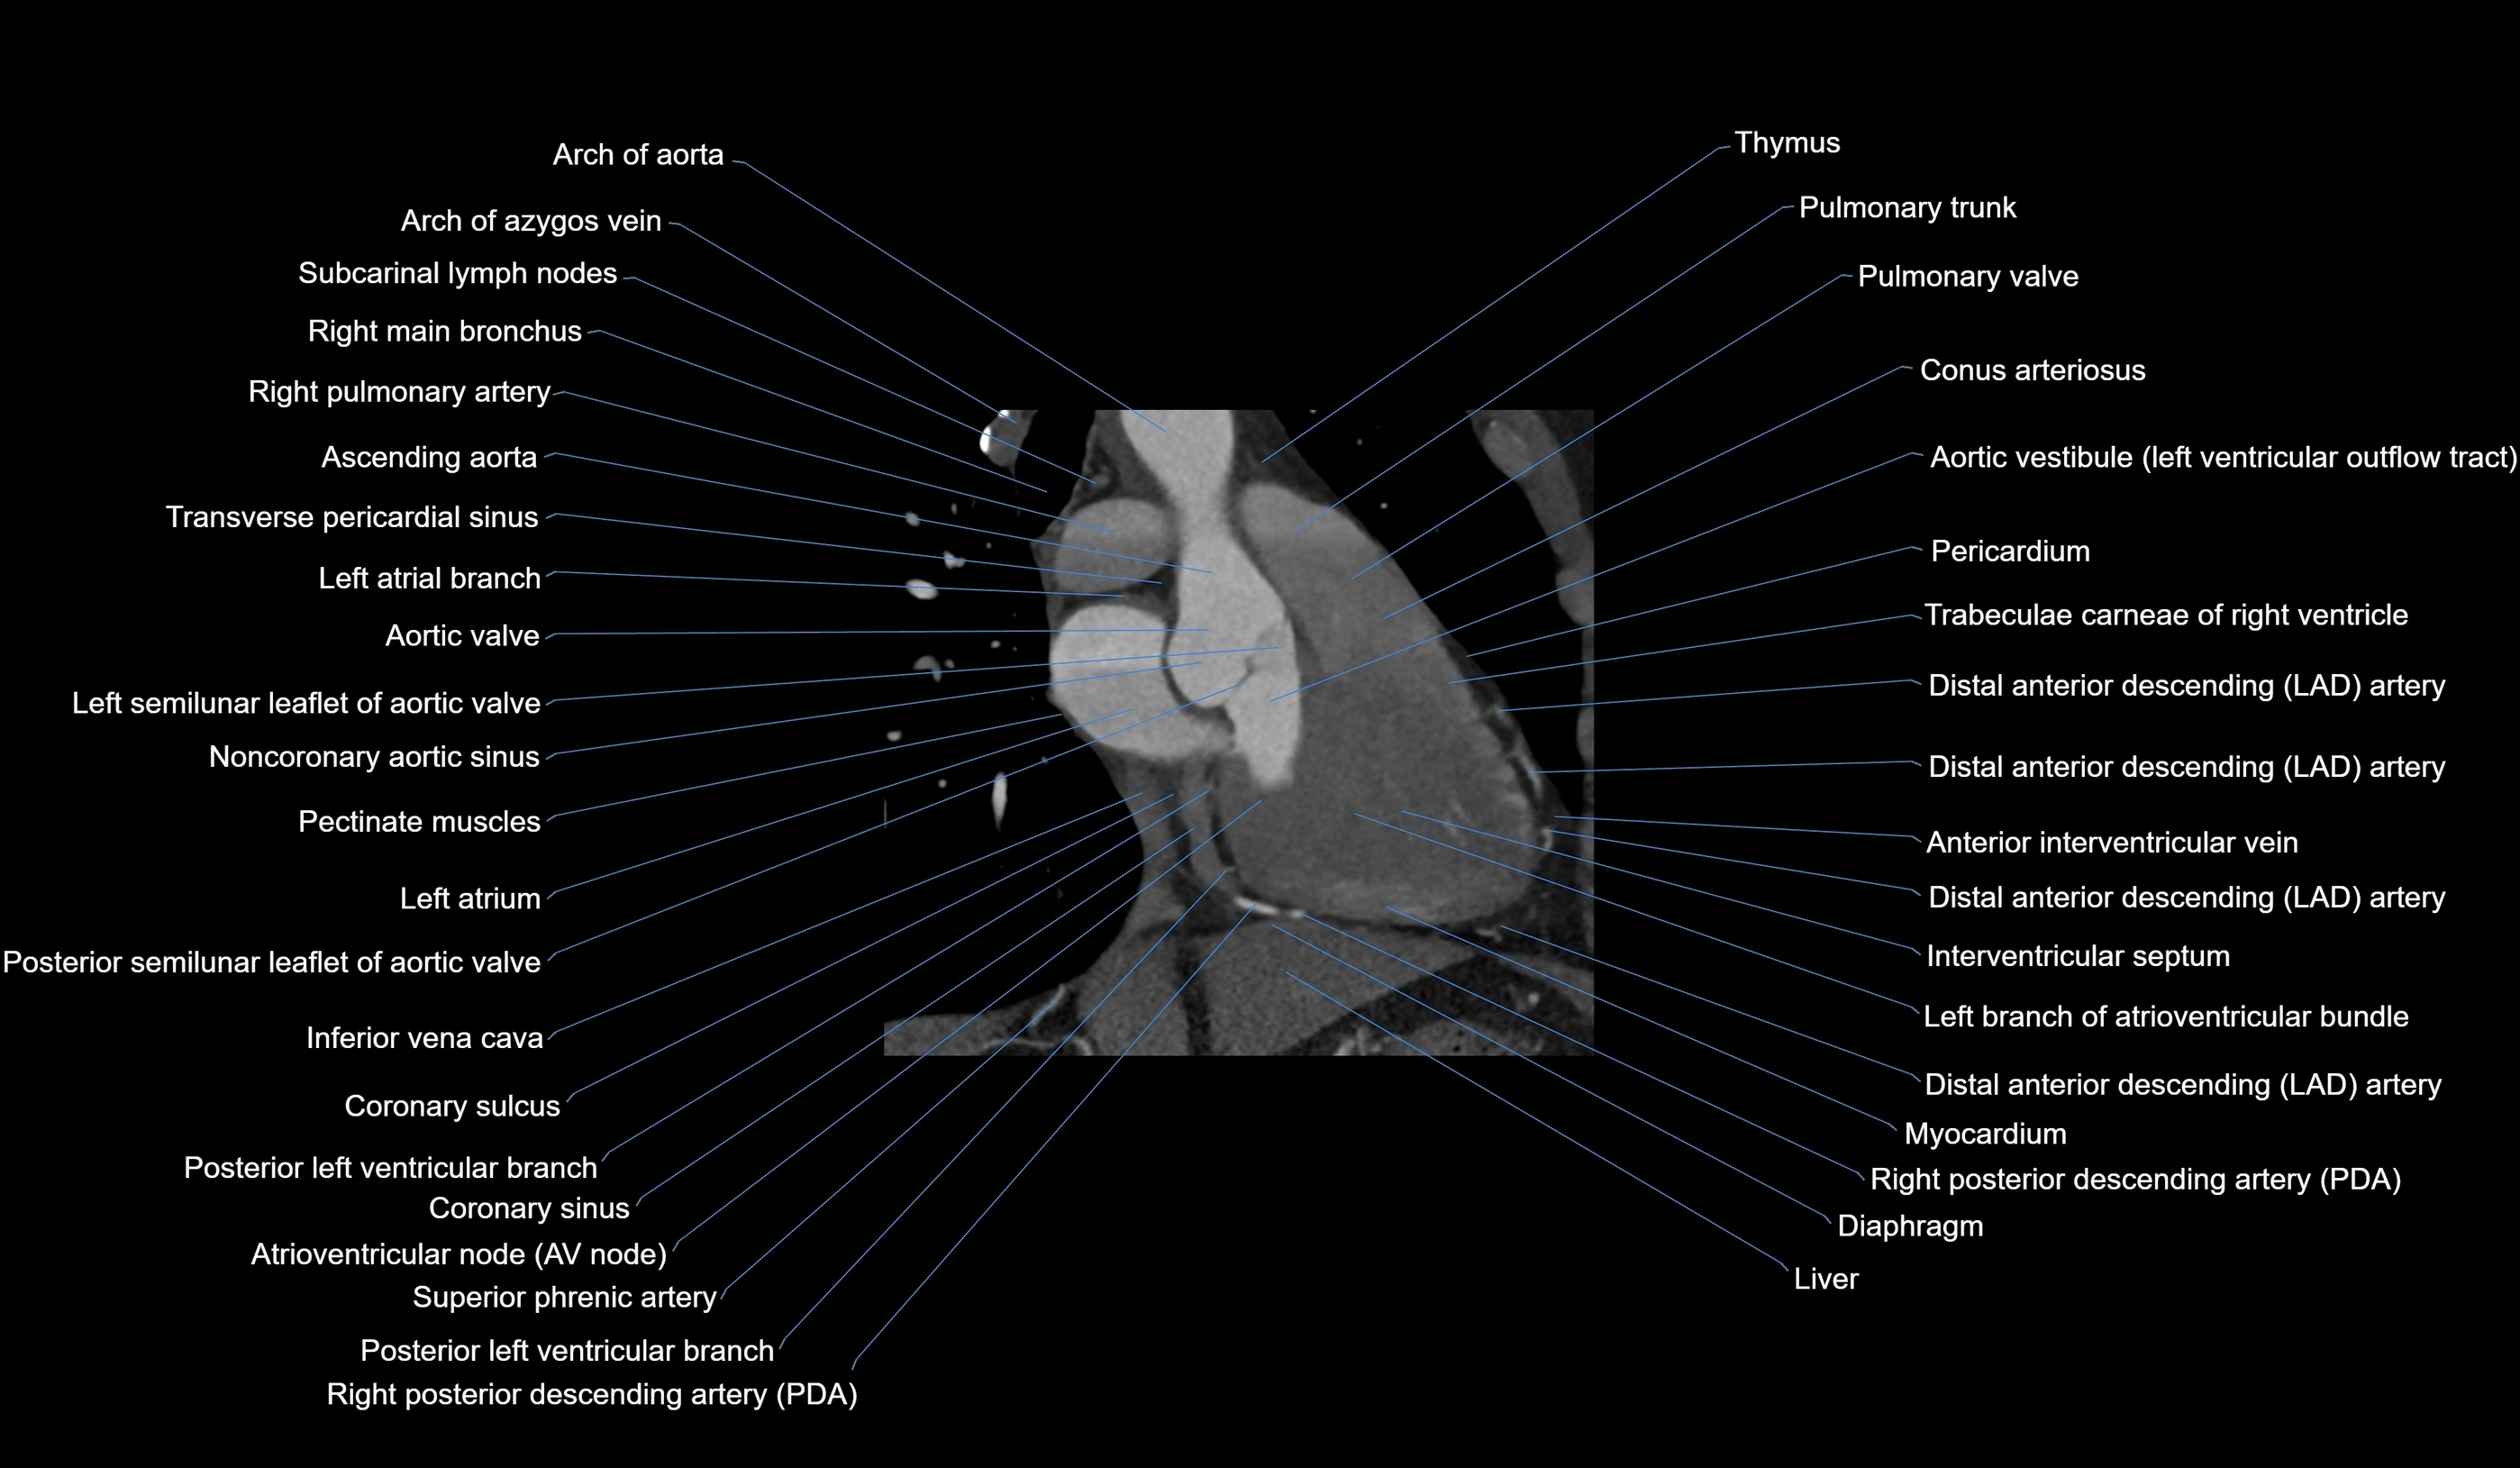

- Arch of aorta

- Azygos vein

- Subcarinal lymph nodes

- Right main bronchus

- Right pulmonary artery

- Ascending aorta

- Transverse pericardial sinus

- Left atrial branch (coronary artery)

- Aortic valve

- Left coronary aortic sinus

- Noncoronary aortic sinus

- Pectinate muscles

- Left atrium

- Posterior leaflet of left atrioventricular valve

- Inferior vena cava

- Coronary sulcus

- Posterior vein of left ventricle

- Coronary sinus

- Atrioventricular Node (AV Node)

- Conus arteriosus

- Pulmonary trunk

- Pulmonary valve

- Aortic vestibule

- Pericardium

- Trabeculae carneae

- Distal left anterior descending artery (dLAD)

- Great cardiac vein

- Interventricular Septum

- Left branch of atrioventricular bundle

- Right posterior descending coronary artery (Right PDA)

- Diaphragm

- Left ventricle